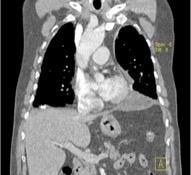

Tromboembolismo pulmonar.

Frecuencia del derrame:

Rx: 32%. TC: 47%

Unilateral. 85%

< 1/3 del hemitórax: 90%

Todos exudados

58% con eritrocitos

21% tabicación lo que causa demora en el diagnóstico

TEP. Empiema pleural. Atelectasia redonda

Porcel JM et al. Analysis of pleural effusions in acute pulmonary embolism: radiological and pleural fluid data from 230 patients. Respirology 2007/ Iguchi T et al. Desquamation of the subpleural lung parenchyma caused by empyema after pulmonary embolism: A case report. Respirol Case Rep. 2022 .

Derrame pleural 43-48% de pacientes con embolismo.

< 1/3 de hemitórax: 90%.(puede haber en lado opuesto).

Siempre exudados.

75% de los pacientes con TEP y derrame pleural tienen dolor pleurítico.

La disnea desproporcionada